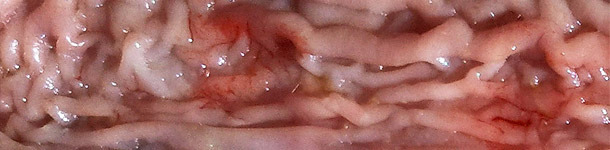

In questo 2° articolo Antonio Vela, Francisco José Pallarés e David Espigares rispondono a domande sulla diagnosi, il monitoraggio e l'eradicazione della pleuropolmonite causata da Actinobacillus pleuropneumoniae (App)...